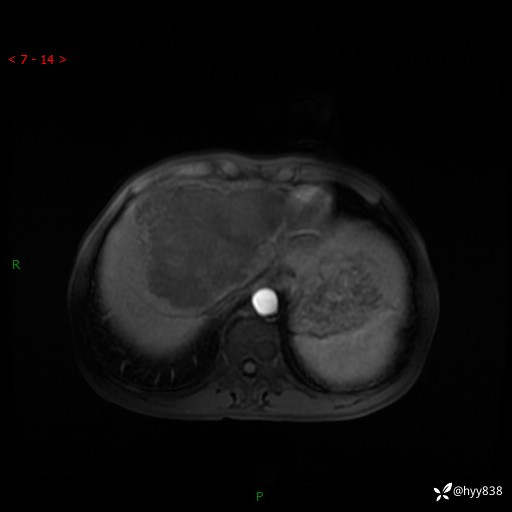

【患者信息】:58岁/男

【主诉】:发现肝占位2天

【现病史及既往史】:患者2天前于当地市第五医院查上腹部磁共振提示:肝脏S4段占位性病变,肝ca可能,胆囊结石,腹膜后多发肿大淋巴结,无剑突下及右上腹疼痛不适,无明显反酸、嗳气,无畏寒、头晕、头痛,无尿频、尿急、尿痛等不适,今为求进一步治疗特来我院就诊,门诊以“肝占位”收住我科。 患者病程中精神、睡眠、饮食尚可,大小便正常、体力体重无明显变化

【检查】:肝脏MRI】平扫+增强